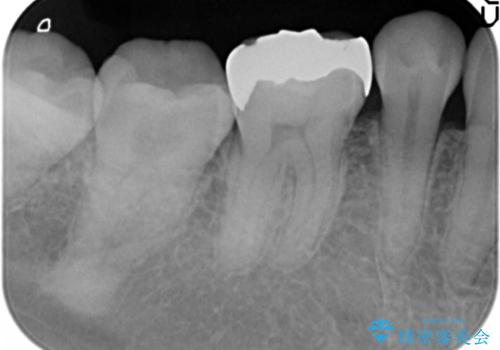

- 笑った際に見える銀歯を白くしたいと希望され来院されました。

銀歯の周囲にも虫歯が見られたのでインレーではなく、耐久性の強いフルジルコニアクラウンでの治療を計画します。

銀歯の周囲に虫歯が再発していたり、内部に虫歯が発生している場合などインレーからクラウン形態へとした方が長期的予後が良い場合があります。